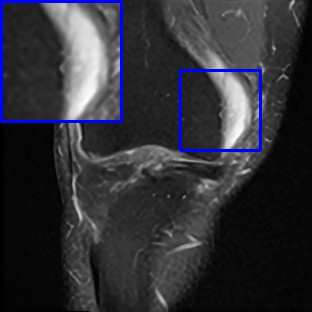

Limited by imaging systems, the reconstruction of Magnetic Resonance Imaging (MRI) images from partial measurement is essential to medical imaging research. Benefiting from the diverse and complementary information of multi-contrast MR images in different imaging modalities, multi-contrast Super-Resolution (SR) reconstruction is promising to yield SR images with higher quality. In the medical scenario, to fully visualize the lesion, radiologists are accustomed to zooming the MR images at arbitrary scales rather than using a fixed scale, as used by most MRI SR methods. In addition, existing multi-contrast MRI SR methods often require a fixed resolution for the reference image, which makes acquiring reference images difficult and imposes limitations on arbitrary scale SR tasks. To address these issues, we proposed an implicit neural representations based dual-arbitrary multi-contrast MRI super-resolution method, called Dual-ArbNet. First, we decouple the resolution of the target and reference images by a feature encoder, enabling the network to input target and reference images at arbitrary scales. Then, an implicit fusion decoder fuses the multi-contrast features and uses an Implicit Decoding Function~(IDF) to obtain the final MRI SR results. Furthermore, we introduce a curriculum learning strategy to train our network, which improves the generalization and performance of our Dual-ArbNet. Extensive experiments in two public MRI datasets demonstrate that our method outperforms state-of-the-art approaches under different scale factors and has great potential in clinical practice.